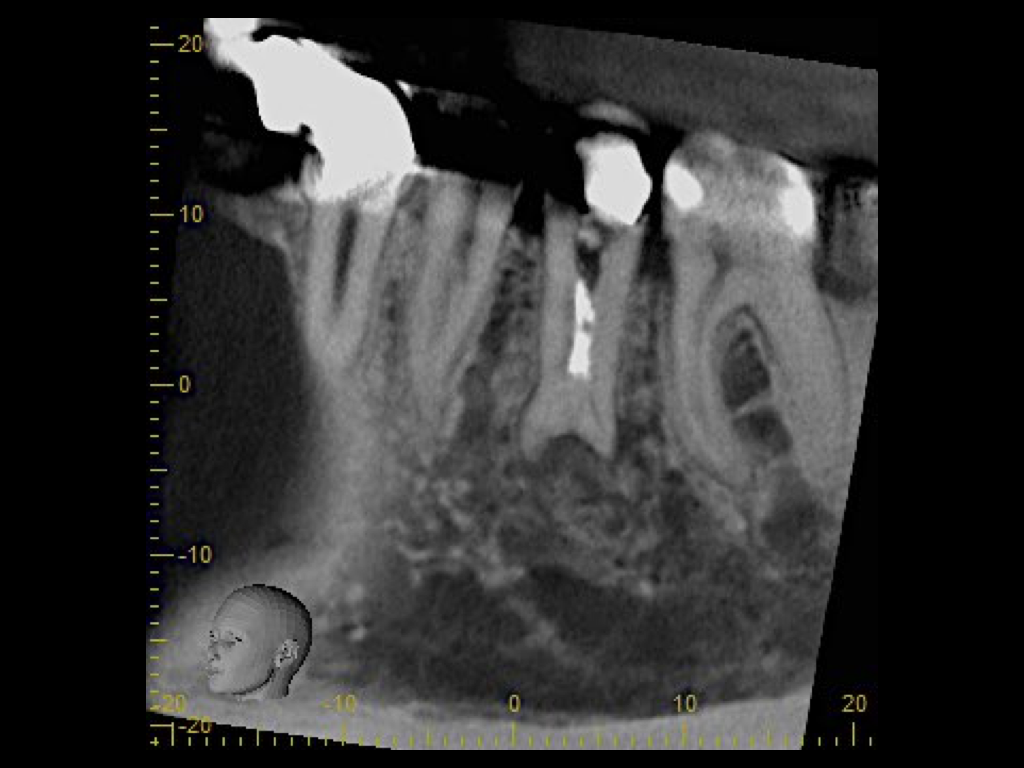

DVT.002

1024 × 768

2015 Fallvorstellung 1